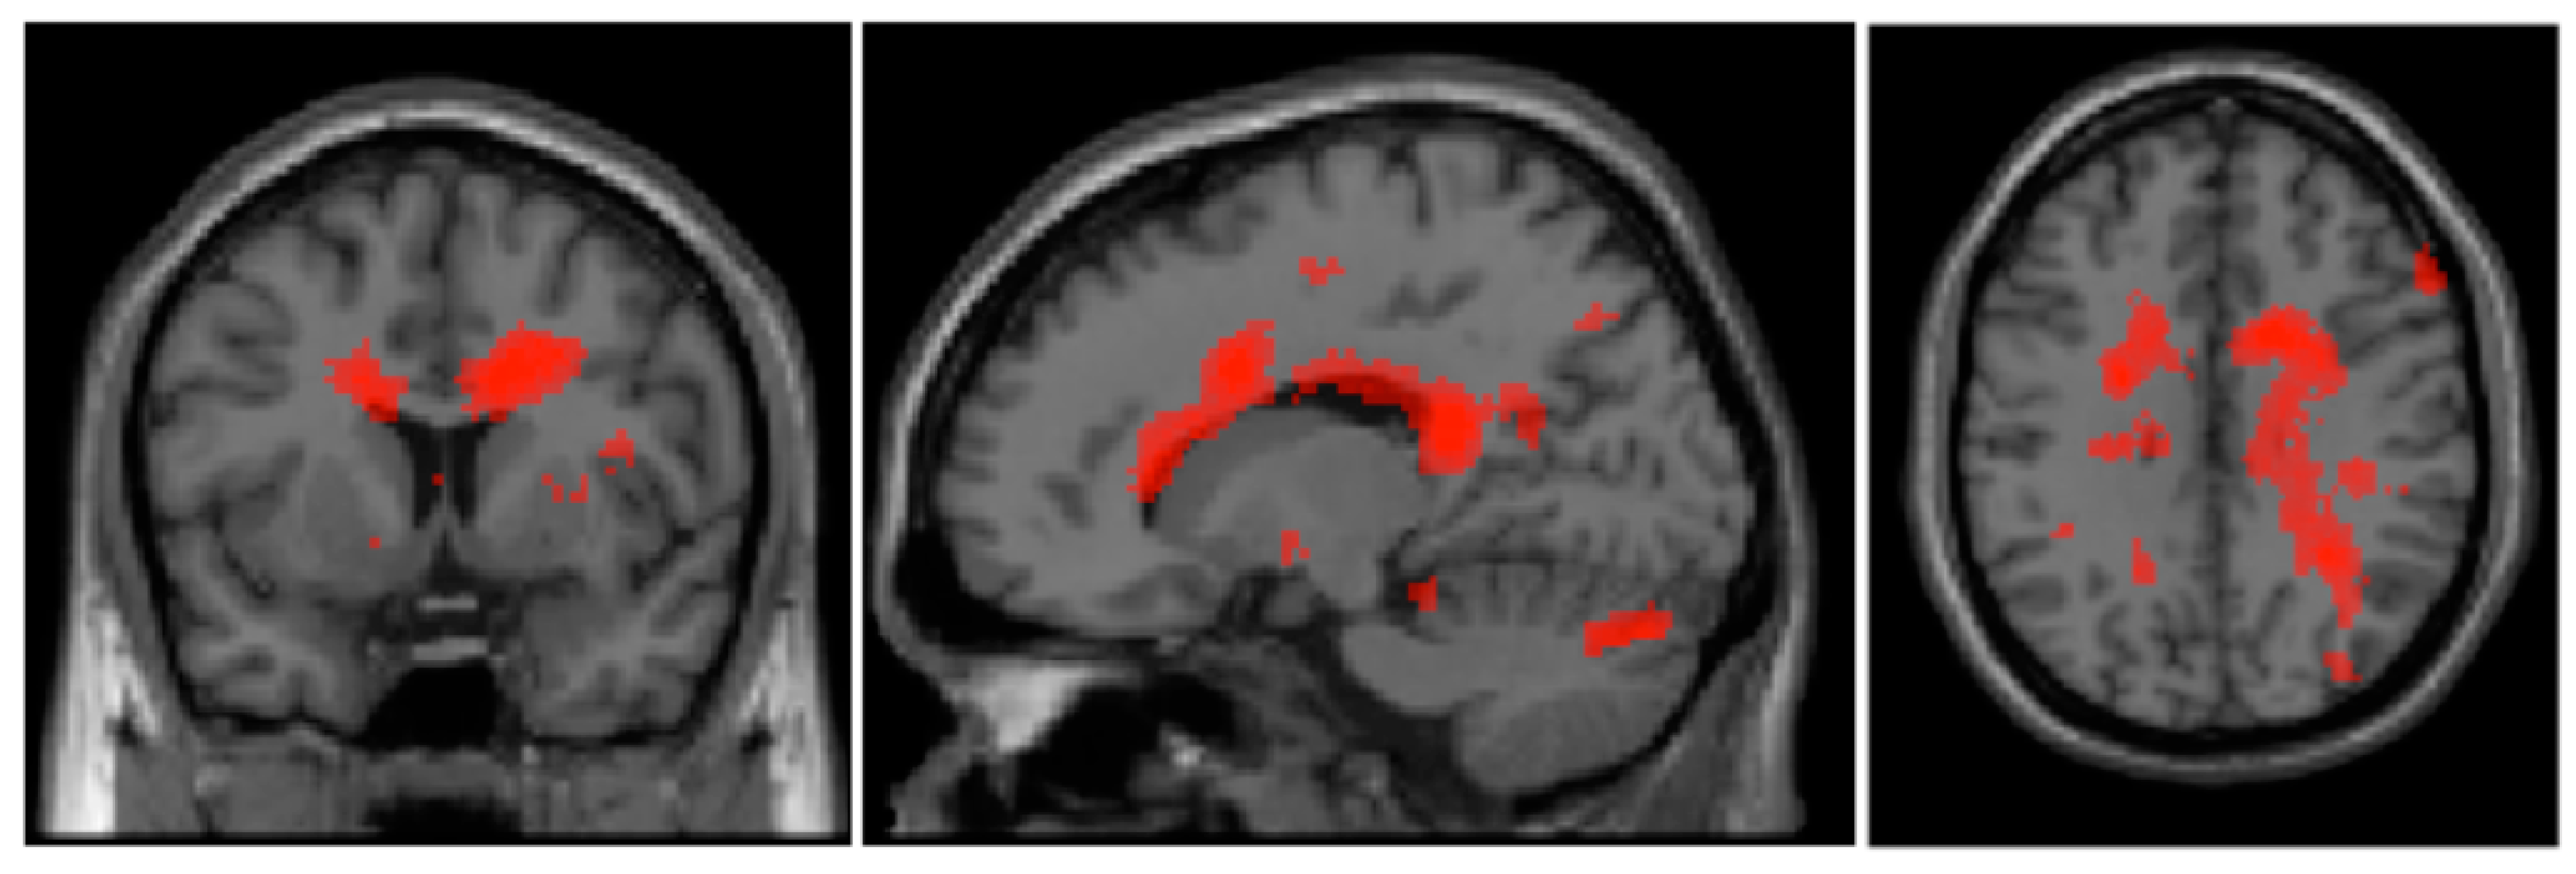

| Cluster | Cluster-Size | Brain Regions | Hemisphere | BA | MNI-Coordinates (x, y, z) | T | ||

|---|---|---|---|---|---|---|---|---|

| Shame: BPD patients > healthy controls | ||||||||

| 1 | 6266 | Gyrus cinguli | R | 24 | 16 | 8 | 32 | 4.12 |

| Cingulum posterior | R | 23 | 14 | −38 | 18 | 4.07 | ||

| Cingulum anterior | R | 33 | 10 | 26 | 12 | 3.58 | ||

| 2 | 1273 | Declive (Cerebellum) | L | * | −30 | −82 | −16 | 3.56 |

| Gyrus fusiformis | R | 19 | 32 | −80 | −10 | 3.46 | ||

| Pyramis (Declive) | R | * | 16 | −80 | −26 | 2.98 | ||

| Shame: healthy controls > BPD patients | ||||||||

| 1 | 1920 | Cuneus | L | 18 | −2 | −94 | 12 | 3.22 |

| Cuneus | L | 18 | −8 | −88 | 32 | 2.70 | ||

| Gyrus lingualis | L | * | −14 | −74 | 6 | 2.63 | ||